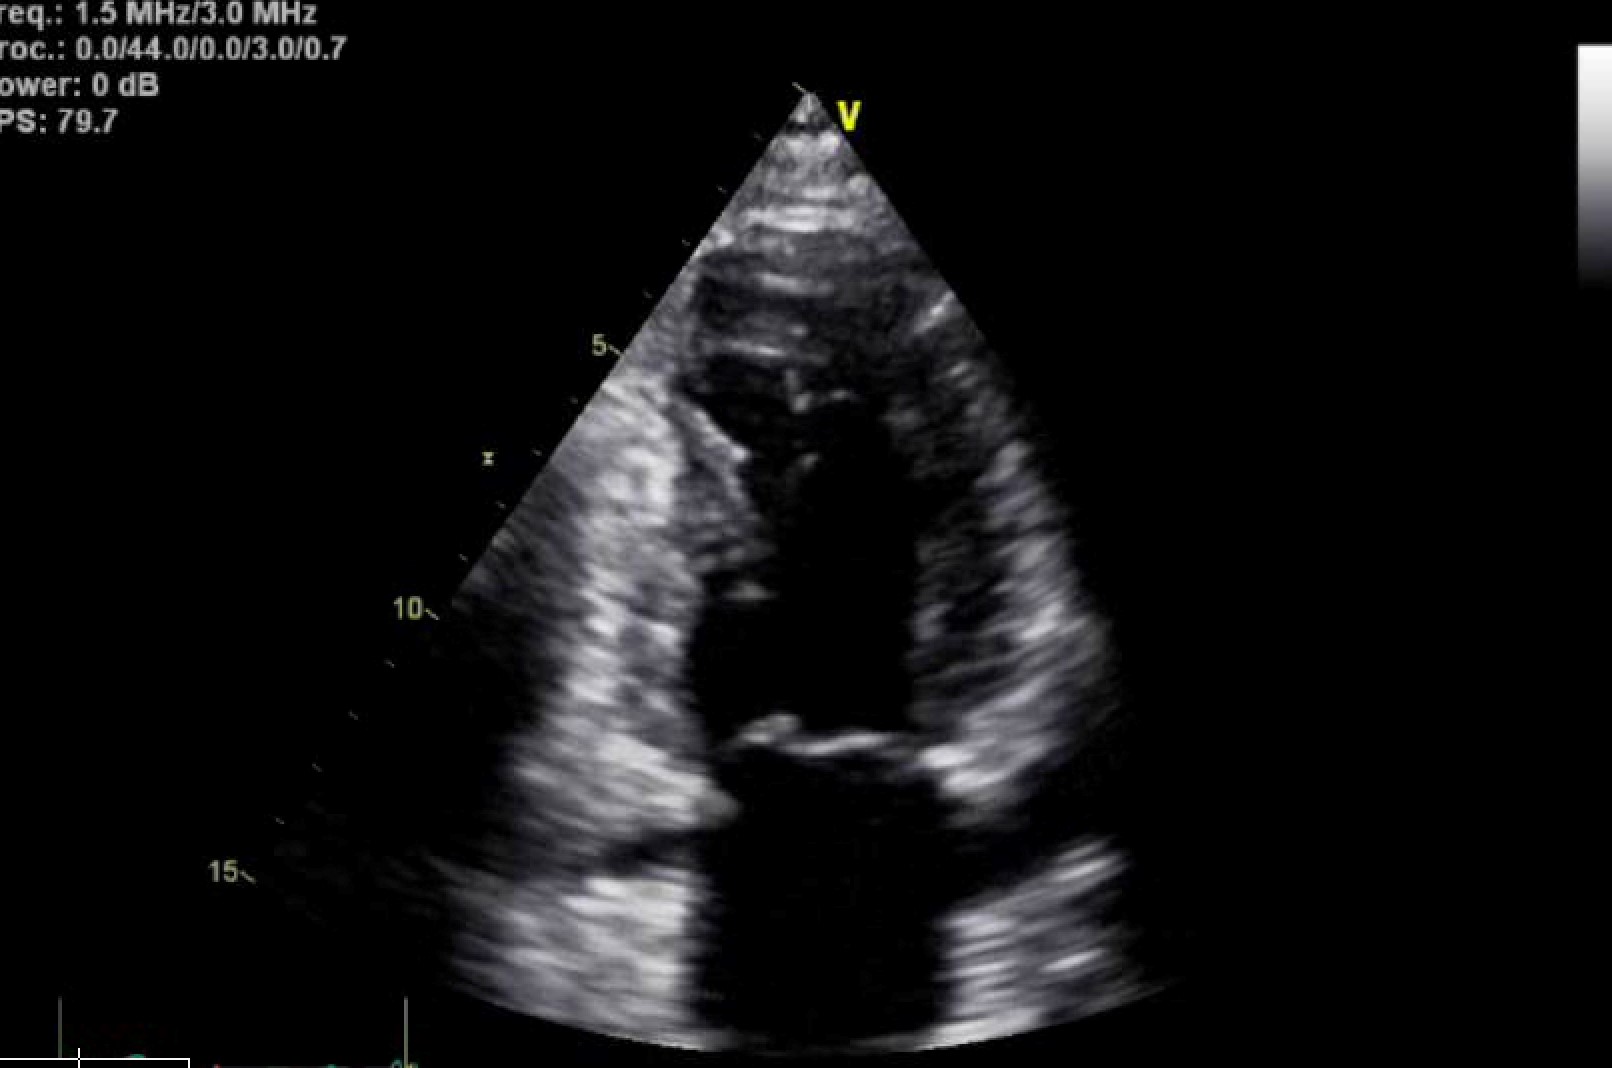

Patient was not in acute distress on non-rebreather mask and mentation was normal. Lungs were clear to auscultation. Cardiac examination revealed normal rate and rhythm without murmurs, rubs, or gallops. Bedside transthoracic echocardiogram was not significant for pericardial effusion or wall motion abnormality.

• Imaging: Transthoracic echocardiogram (TTE) was significant for wall motion abnormalities in the apex, apical-inferior, septal, and apical-anterior myocardial walls. Ejection fraction (EF) was estimated to be 55%. [Figure 2, 3]